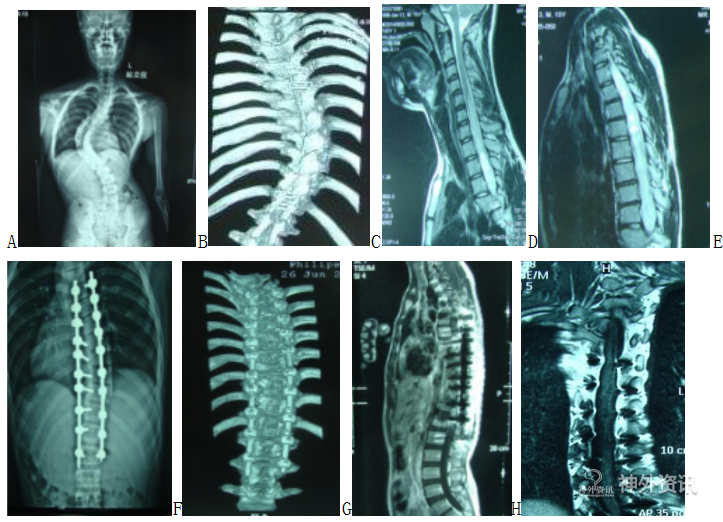

立位平片示:脊柱右侧弯,Cobb角85°。

术前增强MRI:T5-T12脊髓内明显强化,不均匀高信号。

手术方式:胸背后正中入路肿瘤切除术+脊柱侧弯纠正术。

术中所见:镜下见脊髓增粗,脊髓搏动差,沿后正中沟切开脊髓,探查见肿瘤位于髓内,灰黄色,质地软,血供丰富,边界欠清,与脊髓粘连紧密,仔细分离粘连,切除肿瘤大小约20*2.5*2.5cm。

病理诊断:星形细胞瘤,伴有灶片状变性坏死及散在钙化,WHOII级。

A. 术前立位平片;B. 术前三维CT重建;C. 术前MRI矢状位(颈段);D. 术前MRI矢状位(胸段);E. 术后X片;F. 术后三维CT重建;G. 术后MRI矢状位;H. 术后MRI冠位。